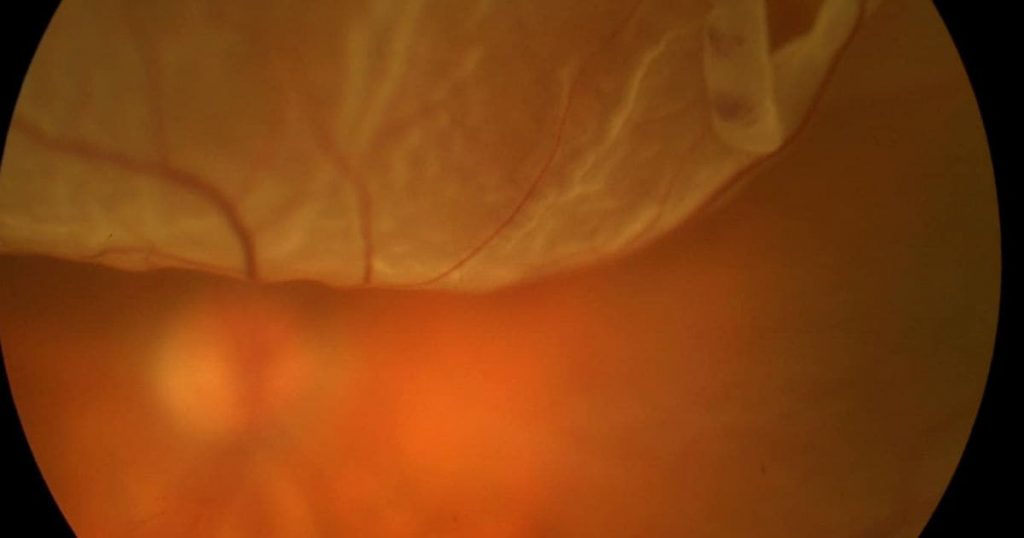

1. Bong võng mạc có chữa được không?

Câu trả lời là: Có. Đa số các trường hợp bị bong võng mạc đều có thể điều trị được. Cụ thể, khả năng điều trị của bệnh bong võng mạc phụ thuộc rất lớn vào thời điểm phát hiện, diện tích vùng bong và tình trạng sức khoẻ của người bệnh . Càng điều trị sớm, cơ hội phục hồi thị lực càng cao. Trong nhiều trường hợp, chỉ sau 1- 3 ngày đến một tuần, võng mạc có thể bị bong hoàn toàn và gây tổn thương vĩnh viễn nếu không được xử lý kịp thời. Vì vậy, ngay khi xuất hiện các dấu hiệu dưới đây người bệnh nên đến bệnh viện thăm khám:

Khi bong võng mạc đã lan rộng hoặc các cách điều trị kể trên không đem lại hiệu quả, bác sĩ sẽ chỉ định mổ mắt bong võng mạc cho bệnh nhân để phục hồi cấu trúc võng mạc và bảo tồn thị lực. Dưới đây là hai phương pháp phẫu thuật điều trị bất thường ở võng mạc phổ biến nhất hiện nay:

- Đây là kỹ thuật phẫu thuật hiện đại nhất trong số các cách điều trị võng mạc bị bong hiện nay. Đặc biệt, nó còn được xem như một trong các lựa chọn duy nhất cho trường hợp bong võng mạc kèm theo xuất huyết dịch kính hoặc bong qua hoàng điểm.